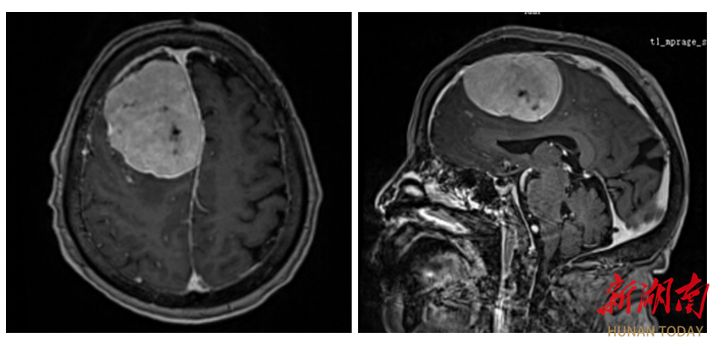

▲患者颅内肿瘤影像。

一个月前,李奶奶病情突然恶化,出现严重食欲减退、意识模糊等症状,家属抱着最后一丝希望,将她送到湖南省第二人民医院脑血管神经外科就诊。入院检查显示,老人右额窦旁的巨大脑膜瘤已严重挤压脑组织,生命体征极不稳定。